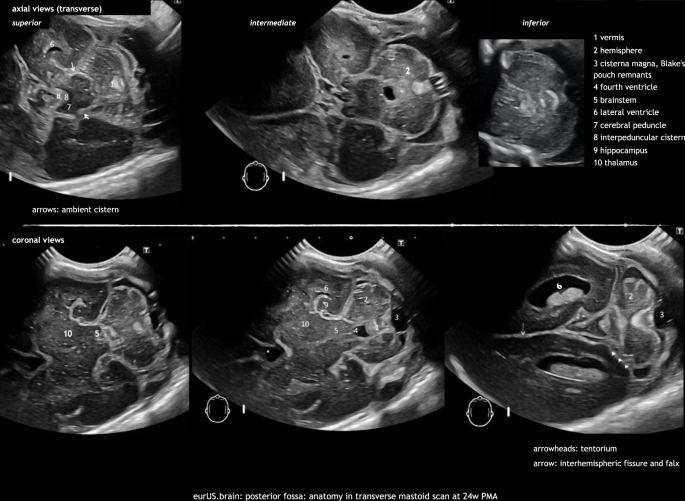

The mastoid fontanel

Several articles have recommended imaging through the mastoid fontanel (MF), also referred to as posterolateral fontanel, to improve ultrasound imaging of the neonatal posterior fossa.9,10,11 With this approach the transducer is placed closer to the posterior fossa structures. Therefore, higher transducer frequencies can be used (8–11 MHz with the standard microconvex probes and even higher, up to 15–18 MHz, with linear probes), thus improving the resolution of the images. Furthermore, the structures are approached from underneath the tentorium and at a more perpendicular angle instead of parallel to the ultrasound beam. This leads to a better visualization of the posterior fossa structures and to a better detection of abnormalities.12,13,14 The MFs are located at the junction of the parietal, temporal, and occipital bones8,9,10,11,15 When performing the examination, the sonographist places the transducer in the mastoid area, behind the helix of the ear and then slightly moves and rotates it to obtain a clear and symmetric view of the posterior fossa. Images are recorded in axial (also transverse) and coronal planes, at different levels.9,10 Cerebellar hemispheres, cerebellar vermis, cisterna magna, the fourth ventricle, and its plexus can be easily visualized through the MF.9,10,16 In addition, the transcerebellar diameter can be measured. The use of color Doppler allows visualization of venous flow in the transverse and sigmoid sinuses: this can be useful in the diagnosis of sinovenous thrombosis.17,18 In our experience, neonates can show some signs of discomfort during MF sonography. This may be explained by an auditory response to pulses of radiofrequency energy.19 Therefore, we advise to perform these views at the end of the CUS examination. Often the whole posterior fossa can be scanned through one single side MF (the one most easily accessible). The opposite MF can be used to confirm or exclude any suspected abnormalities, during the same or a subsequent examination. Usually the approach only costs a few minutes of additional scanning time.